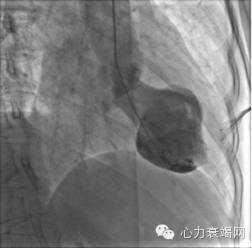

#2.入院后患者行冠状动脉造影,影像学显示轻度冠状动脉远端病灶;行左侧脑室RAO视图,示收缩期心室功能异常

心导管检查显示左心室造影收缩时,中室与顶端收缩膨胀。